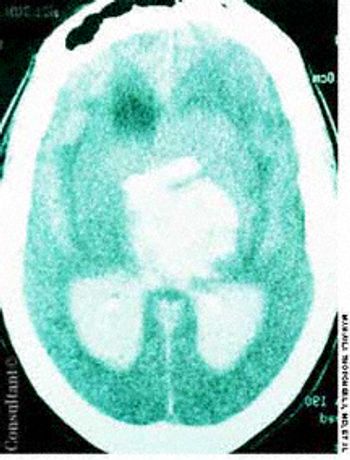

Police brought a delirious, combative 24-year-old man to the emergency department. The patient was unable to provide any history on arrival, but his scarred, blistering lips and his vital signs (blood pressure, 166/102 mm Hg; heart rate, 97 beats per minute; respiratory rate, 24 breaths per minute; and temperature, 38.2°C, or 100.9°F) led to a possible diagnosis of cocaine-induced delirium.